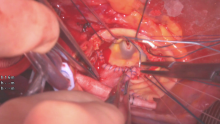

The patient had severe aortic stenosis with heart failure symptoms. Peak and mean gradients across the aortic valve (AV) were 71 and 40 mmHg, respectively. A preoperative CT angiogram (CTA) showed a root of 34 mm, an ascending aorta of 39 mm, and severe longitudinal calcification of the ascending aorta. A median sternotomy was performed with aortic cannulation at the distal ascending and proximal arch. A complete transverse aortotomy was made approximately 2 cm above the sinotubular junction (STJ) anteriorly and 1 cm above the STJ posteriorly. The aortic root was dissected above the left and right atrium to the level of the dome of the left atrium and the nadir of the noncoronary sinus. The annulus was measured to be 23 mm. A standard Y-incision was made at the left –non-commissure, extending from the aortotomy into the aortomitral curtain, underneath and parallel to the aortic annulus to their respective nadirs, by partially cutting into the left and right fibrous trigones. A 2 x 3 inch (5 x 7.5 cm) rectangular-shaped Hemashield Dacron patch was trimmed to a width 5 mm greater than the distance between the two cusp nadirs on each end.

This patch was sewn to the aortomitral curtain and mitral annulus from the left fibrous trigone to the right fibrous trigone with a running 4-0 Prolene suture. The suture line was transitioned to the aortic annulus at the nadir of both the left and noncoronary sinuses, sutured along the longitudinal length of the patch to the level of the transverse aortotomy incision, and secured with additional 4-0 Prolene sutures. The valve sizer was placed in the enlarged root, touching all three nadirs of the aortic annulus to determine the size of the prosthesis, which was found to be size 29.

The height of the divided left noncommissure was marked on the patch to indicate where the highest suture should be placed, and the size 29 valve sizer was then traced onto the patch. While the patch was pulled upward, the size 29 bioprosthetic valve was placed into the enlarged aortic root with one strut facing the left-right commissure to confirm that the marking of the valve sutures on the patch matched the sewing ring of the bioprosthesis, and the two coronary ostia were not obstructed.

Nonpledgeted 2-0 Ethibond sutures were then placed along the native aortic annulus in a noneverting fashion. The size 29 valve was placed with one strut facing the left-right commissure, and the valve sutures were divided by three and evenly distributed to the sewing ring of the three cusps of the bioprosthetic valve, starting at the left-right commissure. The sutures at the nadirs of the noncoronary and left coronary sinuses, the lowest point of the aortic annulus, were tied first. A longitudinal aortotomy was made in the posterior proximal ascending aorta, and the distal end of the rectangular patch was trimmed in a triangular shape symmetrically, with the tip of the triangle 2-3 cm above the strut. The aortotomy was closed with 4-0 Prolene, incorporating the triangular-shaped end of the patch into the longitudinal aortotomy using the “Roof” technique (3).